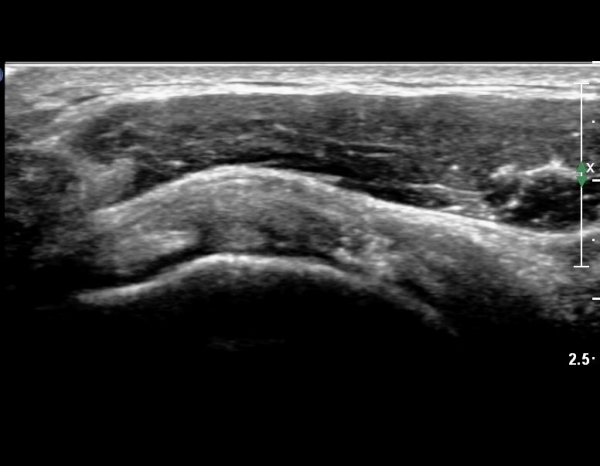

°ß°©ÇÏ±Ù°Ç È¾´Ü¸é°Ë»ç¿¡¼­ °Ç »óºÎ¿¡ ÀÌÁúÀûÀÎ ¿¡ÄÚ¸¦ º¸¿© °ß°©ÇÏ±Ù°Ç »óºÎ ºÎºÐÆÄ¿­ÀÌÃßÁ¤µÈ´Ù(»çÁø 5, 6, 7)